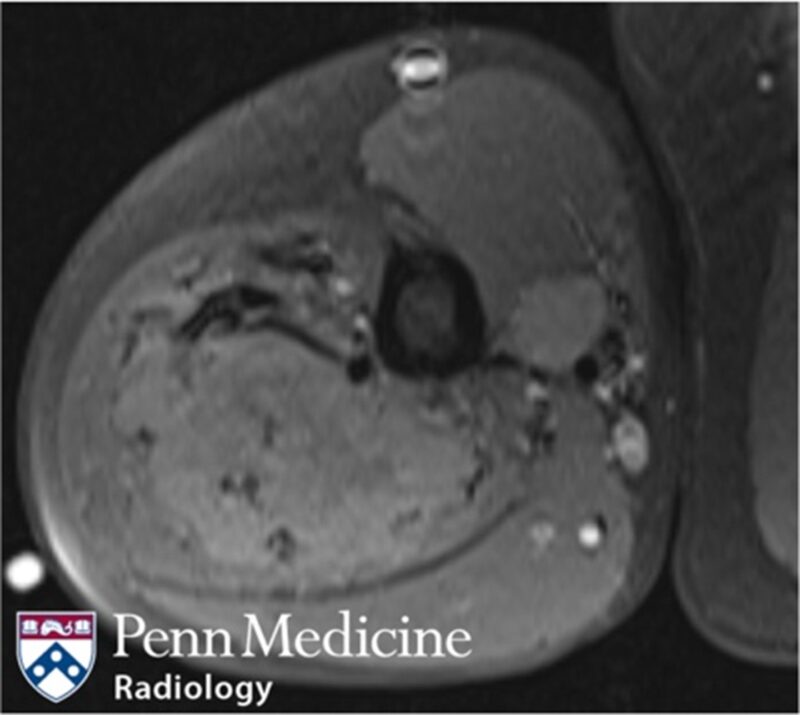

35-year-old woman with progressive pain and swelling in left lower leg

A 35-year-old woman presented to the emergency department with a three-week history of progressive pain and swelling in her left lower leg.

Published Date: February 13, 2026

Tags:

Body

,

CT

MRI

Musculoskeletal

X-Ray